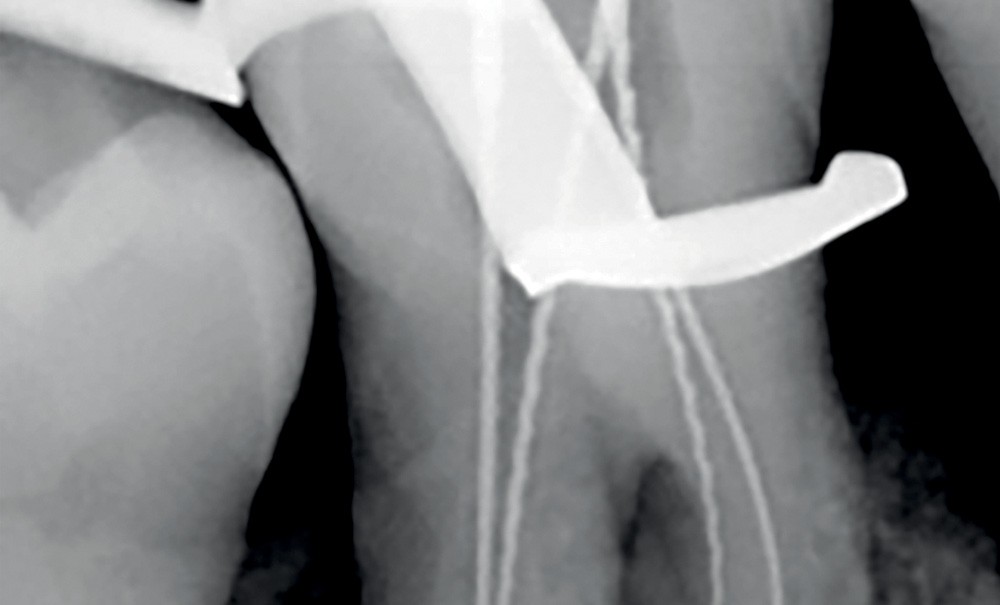

Ce traitement endodontique est associé à un détartrage peu profond et un apprentissage des techniques de contrôle de plaque. Une réévaluation a lieu entre 3 et 6 mois (en fonction de l’évolution de la symptomatologie clinique et radiologique). Pa la suite, en cas d’évolution favorable et après sondage parodontal, des thérapeutiques parodontales complémentaires peuvent être envisagées (fig. 2).

2. Exemple de prise en charge d’une lésion endo-parodontale sans atteinte de l’intégrité radiculaire, chez un patient atteint de parodontite, de grade 3 (poche parodontale profonde sur plus d’une surface dentaire). Le traitement endodontique est réalisé dans un premier temps. Après réévaluation à 6 mois, une contention a été placée et une thérapeutique parodontale complémentaire a pu être réalisée (surfaçage et mise en place de matériaux de comblement). La maintenance parodontale est effectuée régulièrement afin de maintenir le résultat obtenu.